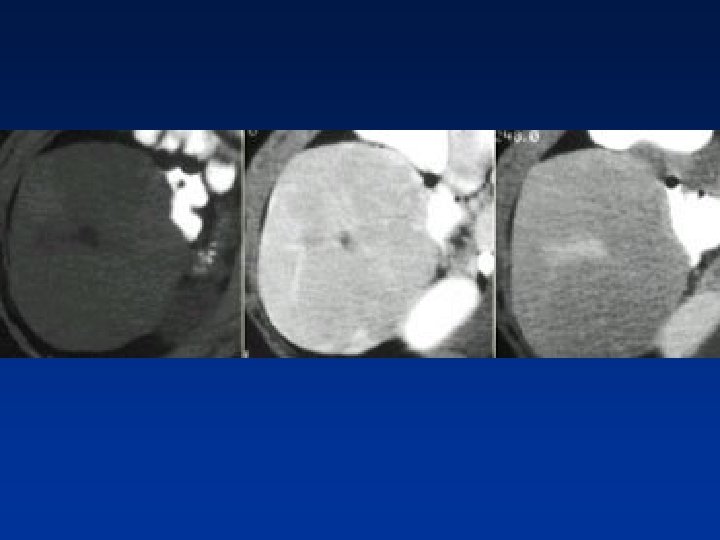

• Giant hemangioma with scar tissue. Notice that the enhancement matches the bloodpool in all phases, central scar is hypodense on NECT & stays hypodense.